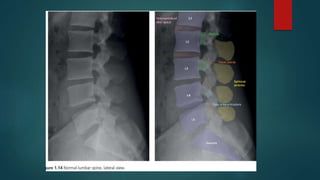

Skeletal X ray anatomy ,colour description, Imaging anatomy of musculoskeletal X rays, Diagnosis imaging anatomay, Radiology